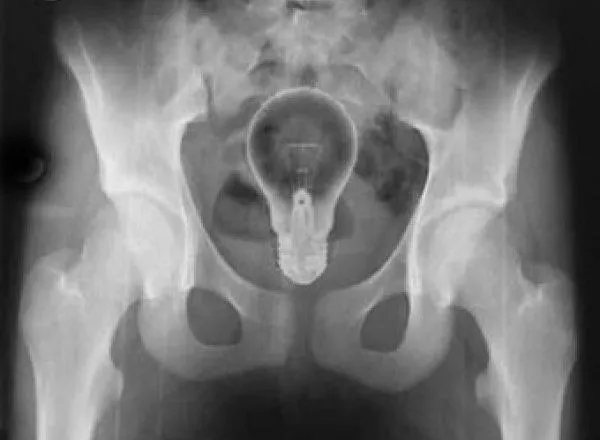

Une poupée

2/9

Là, c"est une poupée qui a été découverte par les médecins lors d"une radiographie. Elle est entrée par l"anus du patient, comme la plupart des objets insolites localisés à cet endroit.